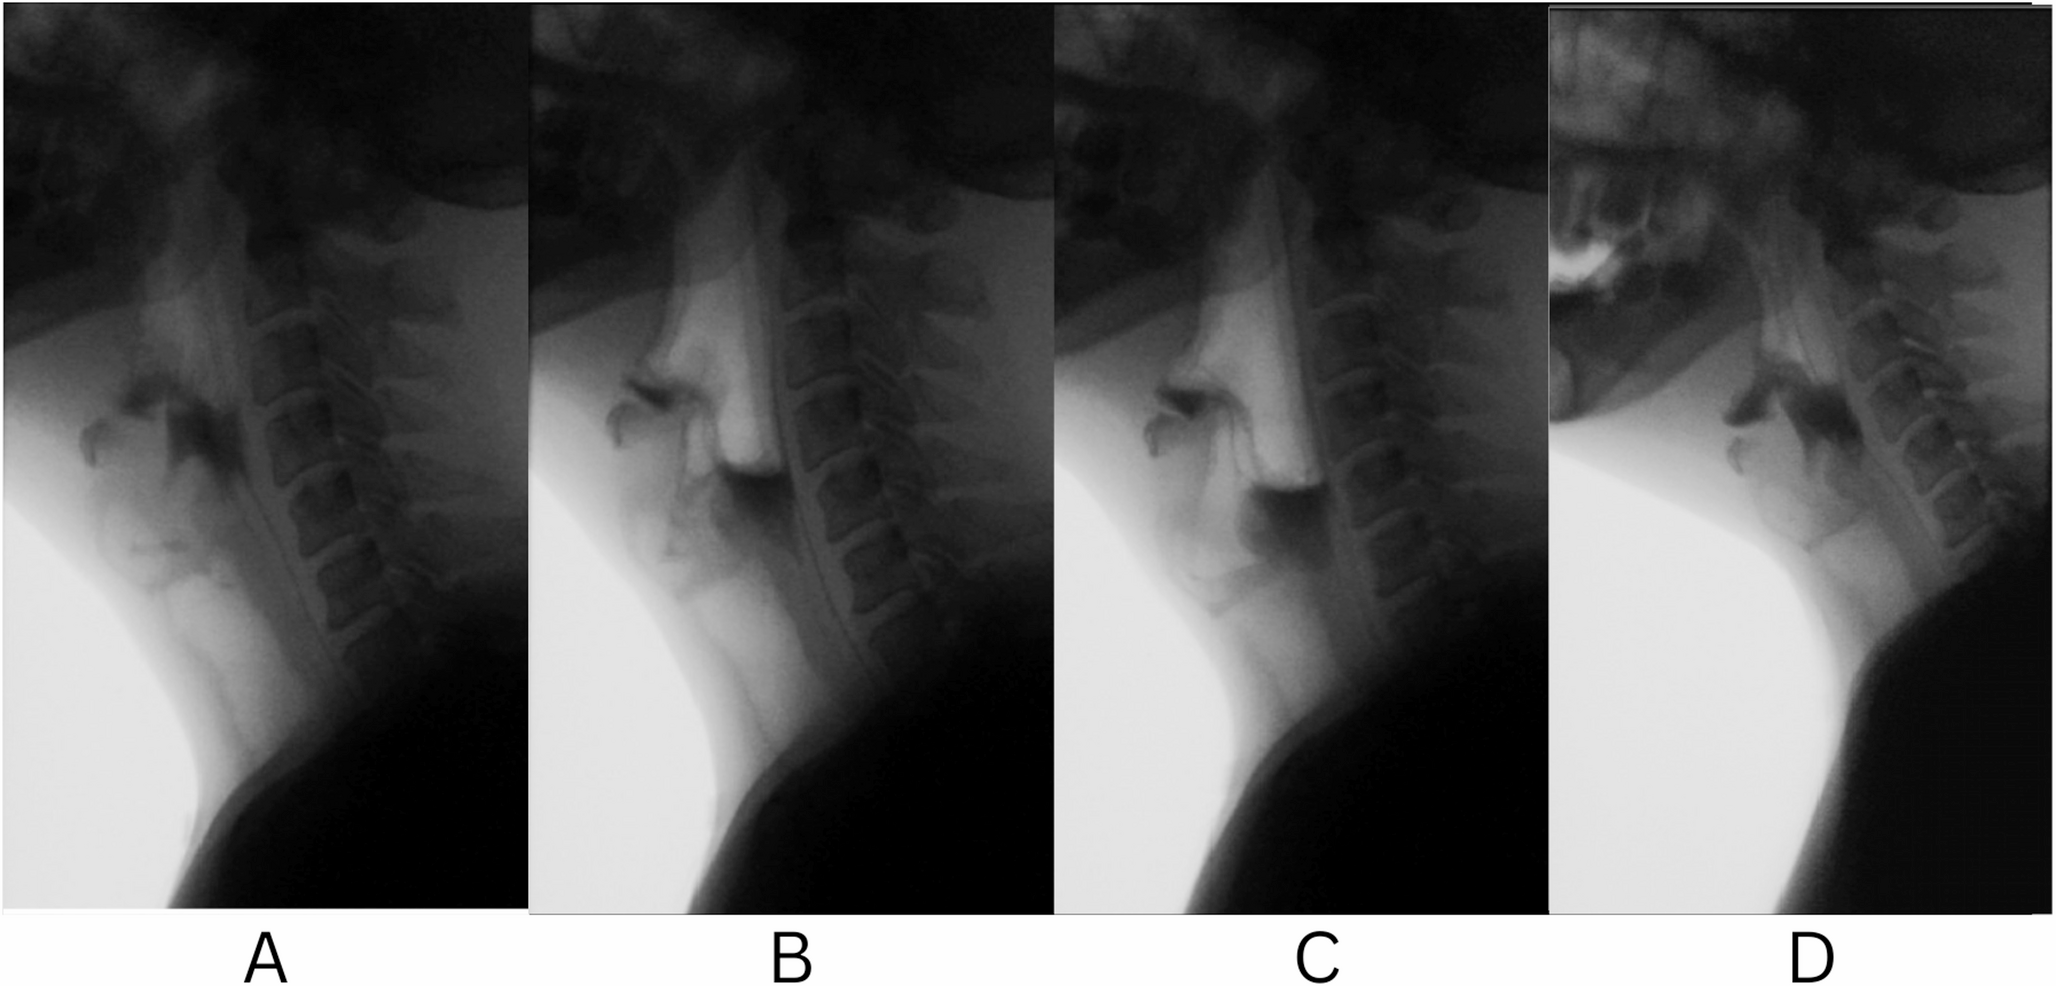

CERVICAL OSTEOPHYTES: A RARE CAUSE OF ACUTE DYSPNEA.

CERVICAL OSTEOPHYTES: A RARE CAUSE OF ACUTE DYSPNEA. Report of 2 cases with different evolution and li...